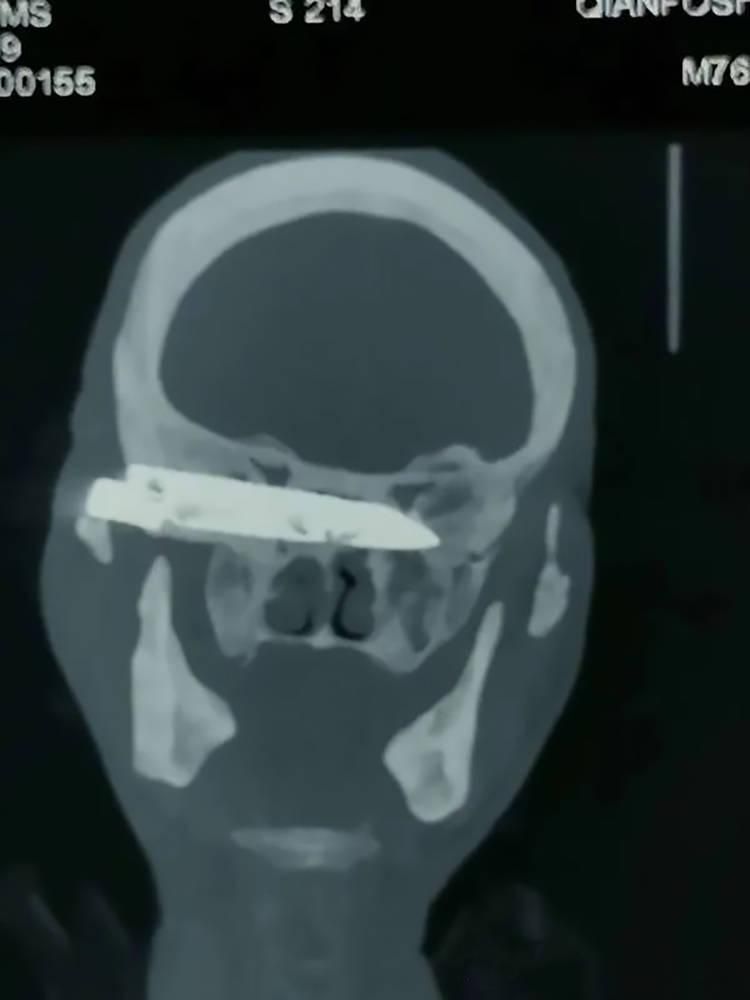

CT scans and X-rays performed at the hospital of Shandong First Medical University in Jinan showed that the blade was located at the base of the patient’s skull, lodged against his eye socket and pressing against his optic nerve. Removing it would be difficult, but according to chief neurosurgeon Dr Liu Guangcun, it was “the only way to resolve the pensioner’s suffering once and for all.”

On April 2 and 8, Duorijie underwent two delicate surgical procedures to have the long knife blade removed.

“During the two-hour surgery, surgeons removed the rusty 10-centimetre (4-inch) blade,” Dr Zhang told reporters. “On April 8, he underwent a second operation to clean his wound. He’s recovering well and can already walk around on his own. His head pains are gone, and he has regained full sight in his right eye. He can also open his mouth and no longer coughs.”